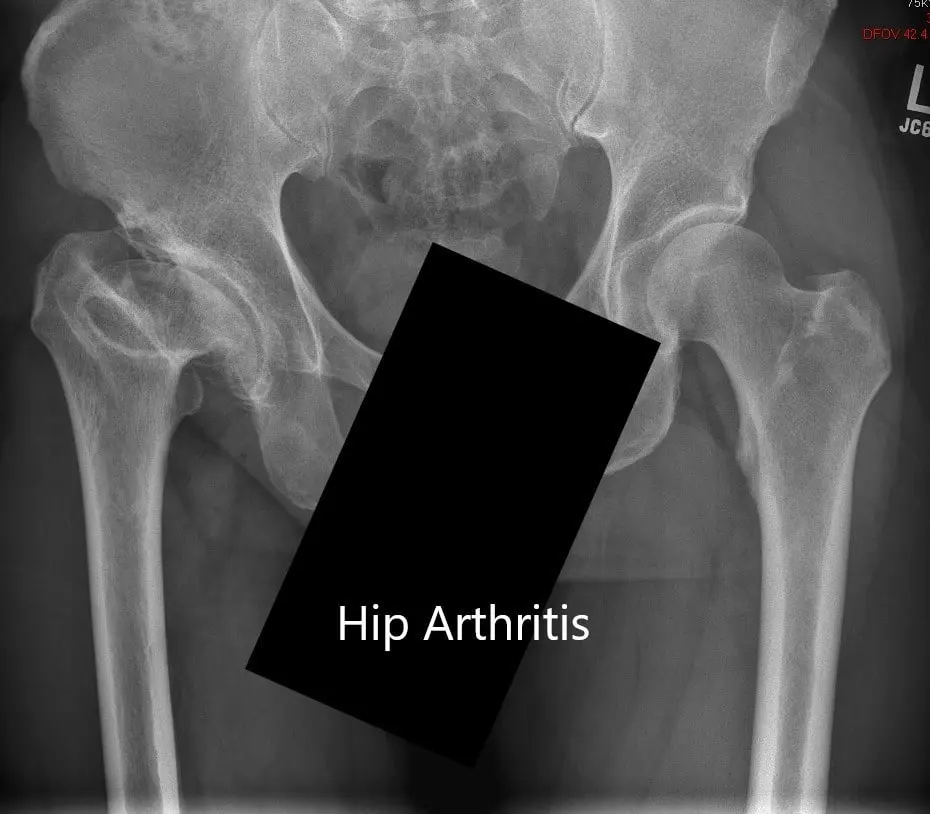

Preoperative X-ray showing the AP view of the pelvis with both hip joints

Imaging revealed markedly deformed right femoral head and impacted the femoral neck. There were severe degenerative changes of the right hip.